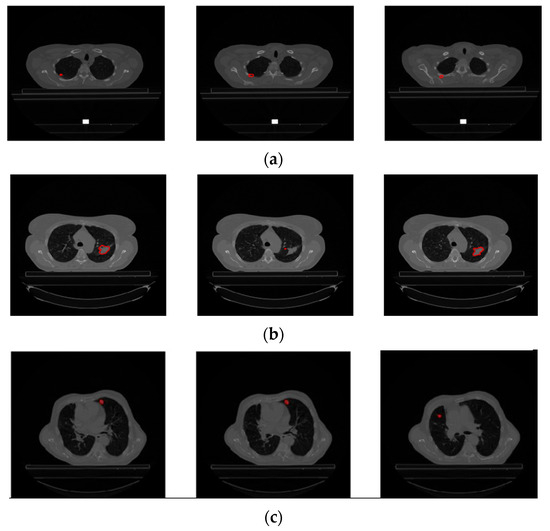

Upon examination of Figure 4, it is evident that GTV-1 information is absent in each slice. As a result of a detailed analysis of the Lung1 dataset, Braghetto stated that 5 patients were incorrectly segmented due to incorrect labeling of tumor regions, 62 patients due to interpolation of segmentation images in consecutive slices, and 3 patients due to the presence of more than one tumor in one image [23]. The representation of each error type is given in Figure 5.

Figure 5. Incorrectly segmented images. (a) Incorrect labeling of tumor regions (LUNG1-158), (b) interpolation of segmentation images in consecutive slices (LUNG1-127), (c) presence of more than one tumor in an image (LUNG1-326).